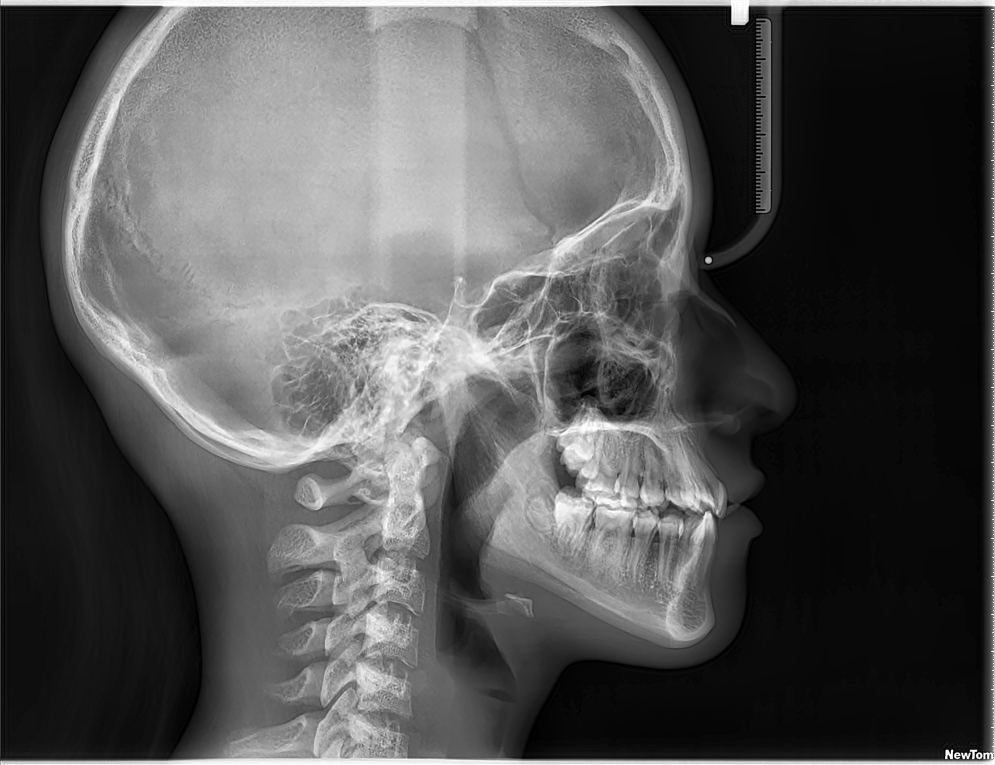

Ofrecemos estudios cefálicos de alta precisión.

Ideales para estudios ortodónticos, estas imágenes permiten evaluar la relación entre los dientes, los huesos y los tejidos blandos del rostro.